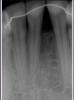

lyubovmuzgina Опубликовано 2 июня, 2013 Поделиться Опубликовано 2 июня, 2013 Как восстановить межзубной сосочек между 31-41.Результат ортодонтического лечения. Ссылка на комментарий

kriokov Опубликовано 2 июня, 2013 Поделиться Опубликовано 2 июня, 2013 (изменено) нужны фото во рту, снимок этих зубов. Изменено 2 июня, 2013 пользователем kriokov 1 Ссылка на комментарий

lyubovmuzgina Опубликовано 2 июня, 2013 Автор Поделиться Опубликовано 2 июня, 2013 точно! ну так на одном симпозиуме были ))сосочка нет совсем, визуально - равнобедренный треугольник с ровным основанием слизистой Ссылка на комментарий

lyubovmuzgina Опубликовано 16 июня, 2013 Автор Поделиться Опубликовано 16 июня, 2013 Пожалуйста фото. Ссылка на комментарий

sergio Опубликовано 16 июня, 2013 Поделиться Опубликовано 16 июня, 2013 Пожалуйста фото.боюсь, гиалуронка здесь не поможет. Надо еще ортодонту работать... хирургически тоже такое не закрыть... А что, пациентку это волнует? это же неэстетически значимая зона обычно Ссылка на комментарий

Bier Опубликовано 16 июня, 2013 Поделиться Опубликовано 16 июня, 2013 хирургически - неоперабельно, костного пика нет. Виниры + ССТ несколько улучшат ситуацию. 3 Ссылка на комментарий